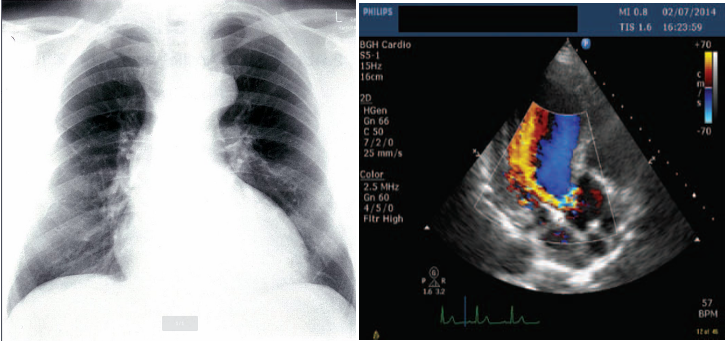

Investigations

- Echocardiography and Doppler (TTE): First-line diagnostic tool: assess the severity: LV dilatation.

- CXR:

- Cardiomegaly: Dilating ascending aorta.

- Pulmonary edema (Acute AR) with normal cardiac size.; crepitation

Findings specific to acute AR: CXR

- Reduced cardiac output.

- Elevated end-diastolic left ventricular pressure.

- Early mitral valve closing.

- (Regurgitant jet is diagnostic).

Imaging

A. Echocardiogram:

- Allows visualization of the origin of the regurgitant jet and its width, detection of aortic valve pathology and ventricular hypertrophy.

B. CXR:

- May demonstrate cardiomegaly.

- Dilated ascending aorta.

- Calcification may be seen.

A 30-year-old woman presented with shortness of breath on exertion and occasional chest pain. Does not use tobacco, alcohol, or illicit drugs. She immigrated from Peru two years ago with her family. Her temperature is 36.4°C; pulse is 115/min, respirations are 24/min, and blood pressure is 130/60 mm Hg. Physical examination shows pulsations of the nail bed. Cardiac examination shows an abnormal heart sound over the left sternal border on auscultation (see image below). Which of the following maneuvers will likely decrease the intensity of this heart sound?